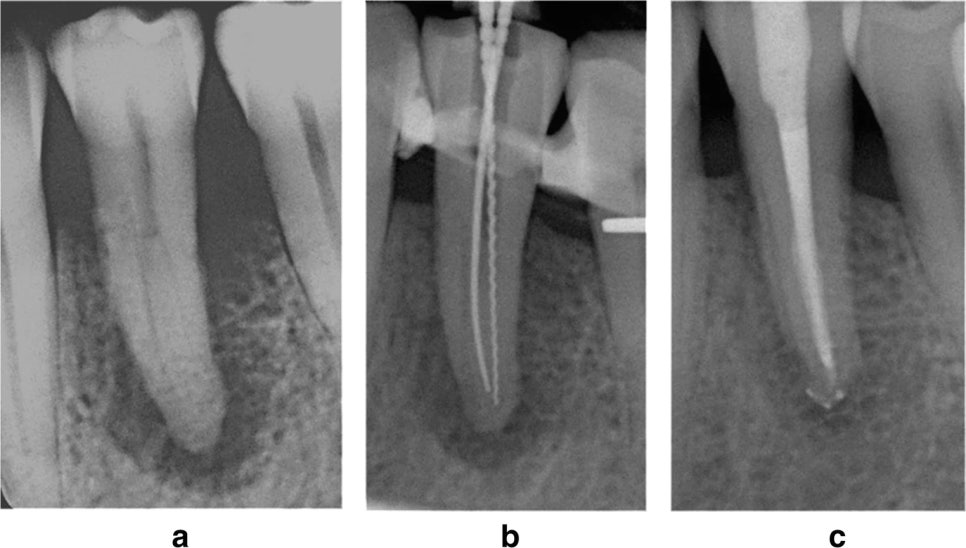

Maurice Ruetters et al., Effect of endodontic treatment on periodontal healing of grade 3 endo-periodontal lesions without root damage in periodontally compromised patients—a retrospective pilot study, Clinical Oral Investigations volume 25, pages2373–2380 (2021) Fig1.

집에 와서 계속 이런 증례 논문을 찾아봤다. endo-perio lesion 즉, 치수-치주 복합 병소에서 근관치료를 성공시킨 증례들.. 내가 어제 맡은 환자분 치아도 단근치니까 가능하지 않을까 해서 희망을 가지고 폭풍 검색. 위 논문 증례도 인접치에 스플린팅 해서 동요도 잡아주고 엔도(b) 해서 6개월 후 F/U한 사진(c)이다. 다른 논문에서도 9개월 F/U, 15개월 F/U 증례도 찾을 수 있었다. 후... 나도 해본다!! 이거 살리면 진짜 엄청 뿌듯할 것 같다. 스플린트 붙여놓은 게 잘 버텨줘야 할 텐데.. 환자 factor가 너무 커서 솔직히 성공 가능성은 매우 매우 낮을 것 같다.